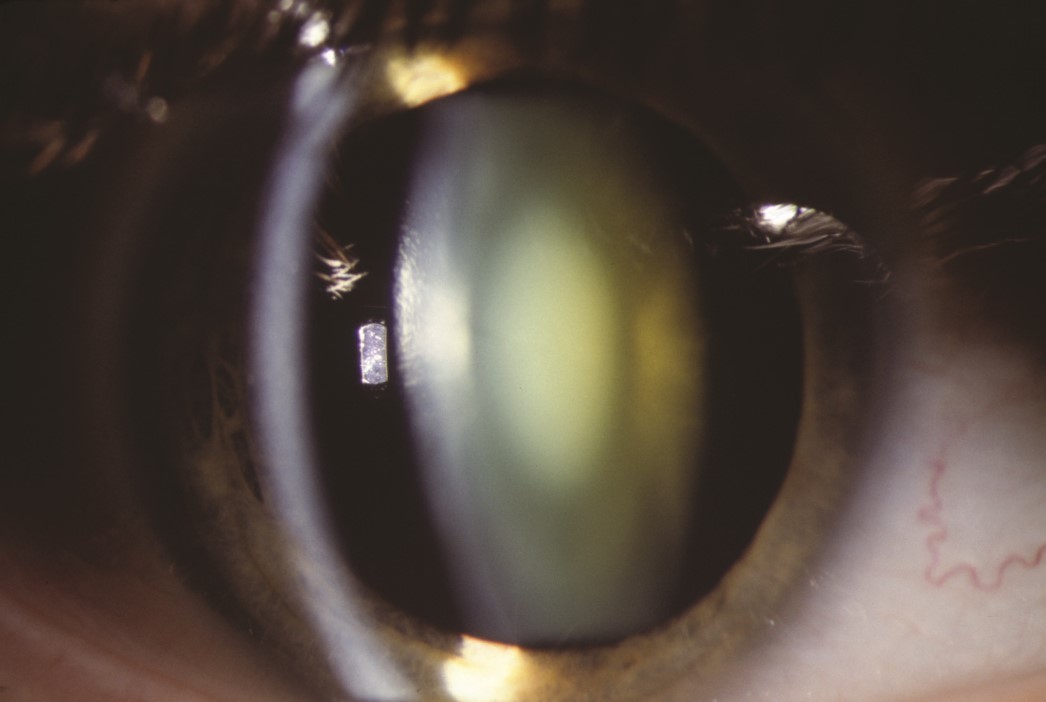

Bilateral “opalescent” nuclear sclerotic cataract. A 38-year-old woman with a long history of multiple sclerosis complained of a gradual decline in the vision of both eyes. This complaint prompted an admission to the hospital and an extensive evaluation including a computed tomography (CT) scan of the head, magnetic resonance imaging (MRI) of brain and orbits, a lumbar puncture, and numerous laboratory studies for presumed optic neuritis. After high-dose intravenous steroids did not help, the patient was referred for neuro-ophthalmic consultation. Not all patients with multiple sclerosis and visual loss have optic neuritis. The basic, routine examination revealed the culprit: bilateral “opalescent” nuclear sclerotic cataract, pictured in this slitlamp photograph. The history and other examination findings supported this diagnosis (myopic shift on refraction, mild diffuse visual field loss). Cataract surgery resulted in 20/20 visual acuity and normalization of a diffusely depressed visual field.

Source: Martin TJ, Corbett JJ. Practical Neuroophthalmology; 2013.